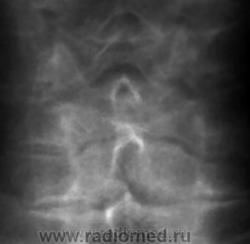

Остеохондроз, спондиллоартроз, протрузия МПД С5-С6 кзади. Что Вас смущает на этих снимках? Игра теней на уровне С6(прямой снимок)?

Если первичный вопрос , есть ли аномалия развития тела позвонка, то я аномалии не вижу. Хочется по прямой проекции указать на С7 как бабочковидный, но не тянет. Мое мнение, что здесь сугубо дегенеративные изменения. А мнение автора?

На теле С5 вероятно изображение унко-вертебрального артроза. Это его законное место. В прямой проекции вообще толком ничего не видно. Снимки очень неважные. Почему ваши лаборанты так широко раскрыли диафрагму? Качество очень страдает. Если есть сомнения в бабочковидном позвонке, можно сделать прямую томограмму.

Щель то щелью, но она должна располагаться посредине тела, а здесь несколько смещена каудально. Кроме того, если в грудном и поясничном отделах сосудистая щель или канал встречаются очень часто, то в шейных позвонках не разу не видела.